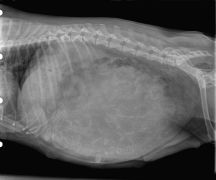

Radio abdominale

Mégaoesophage

Fécalome

radiographie de gestation chienne

Radiographie de gestation